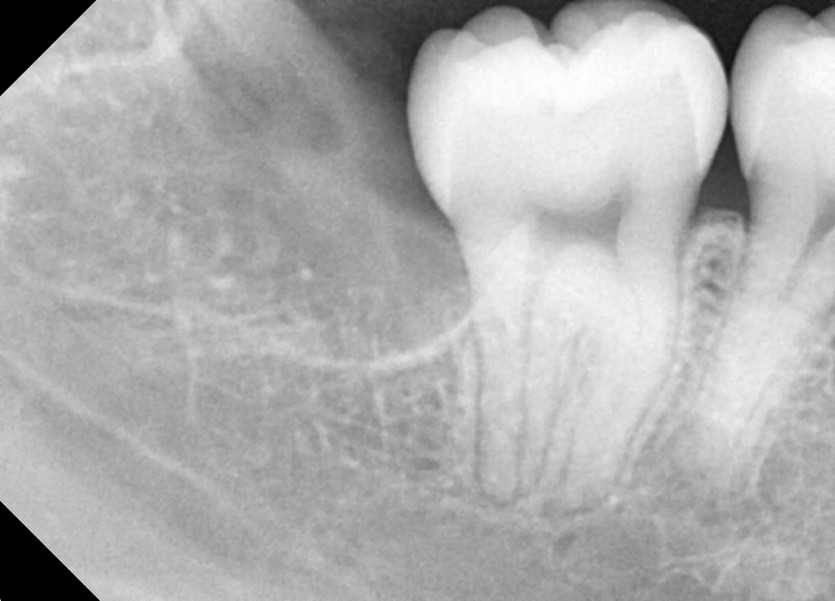

#38,48 사랑니 발치

구강 외과 전문의가 당일 발치했습니다.